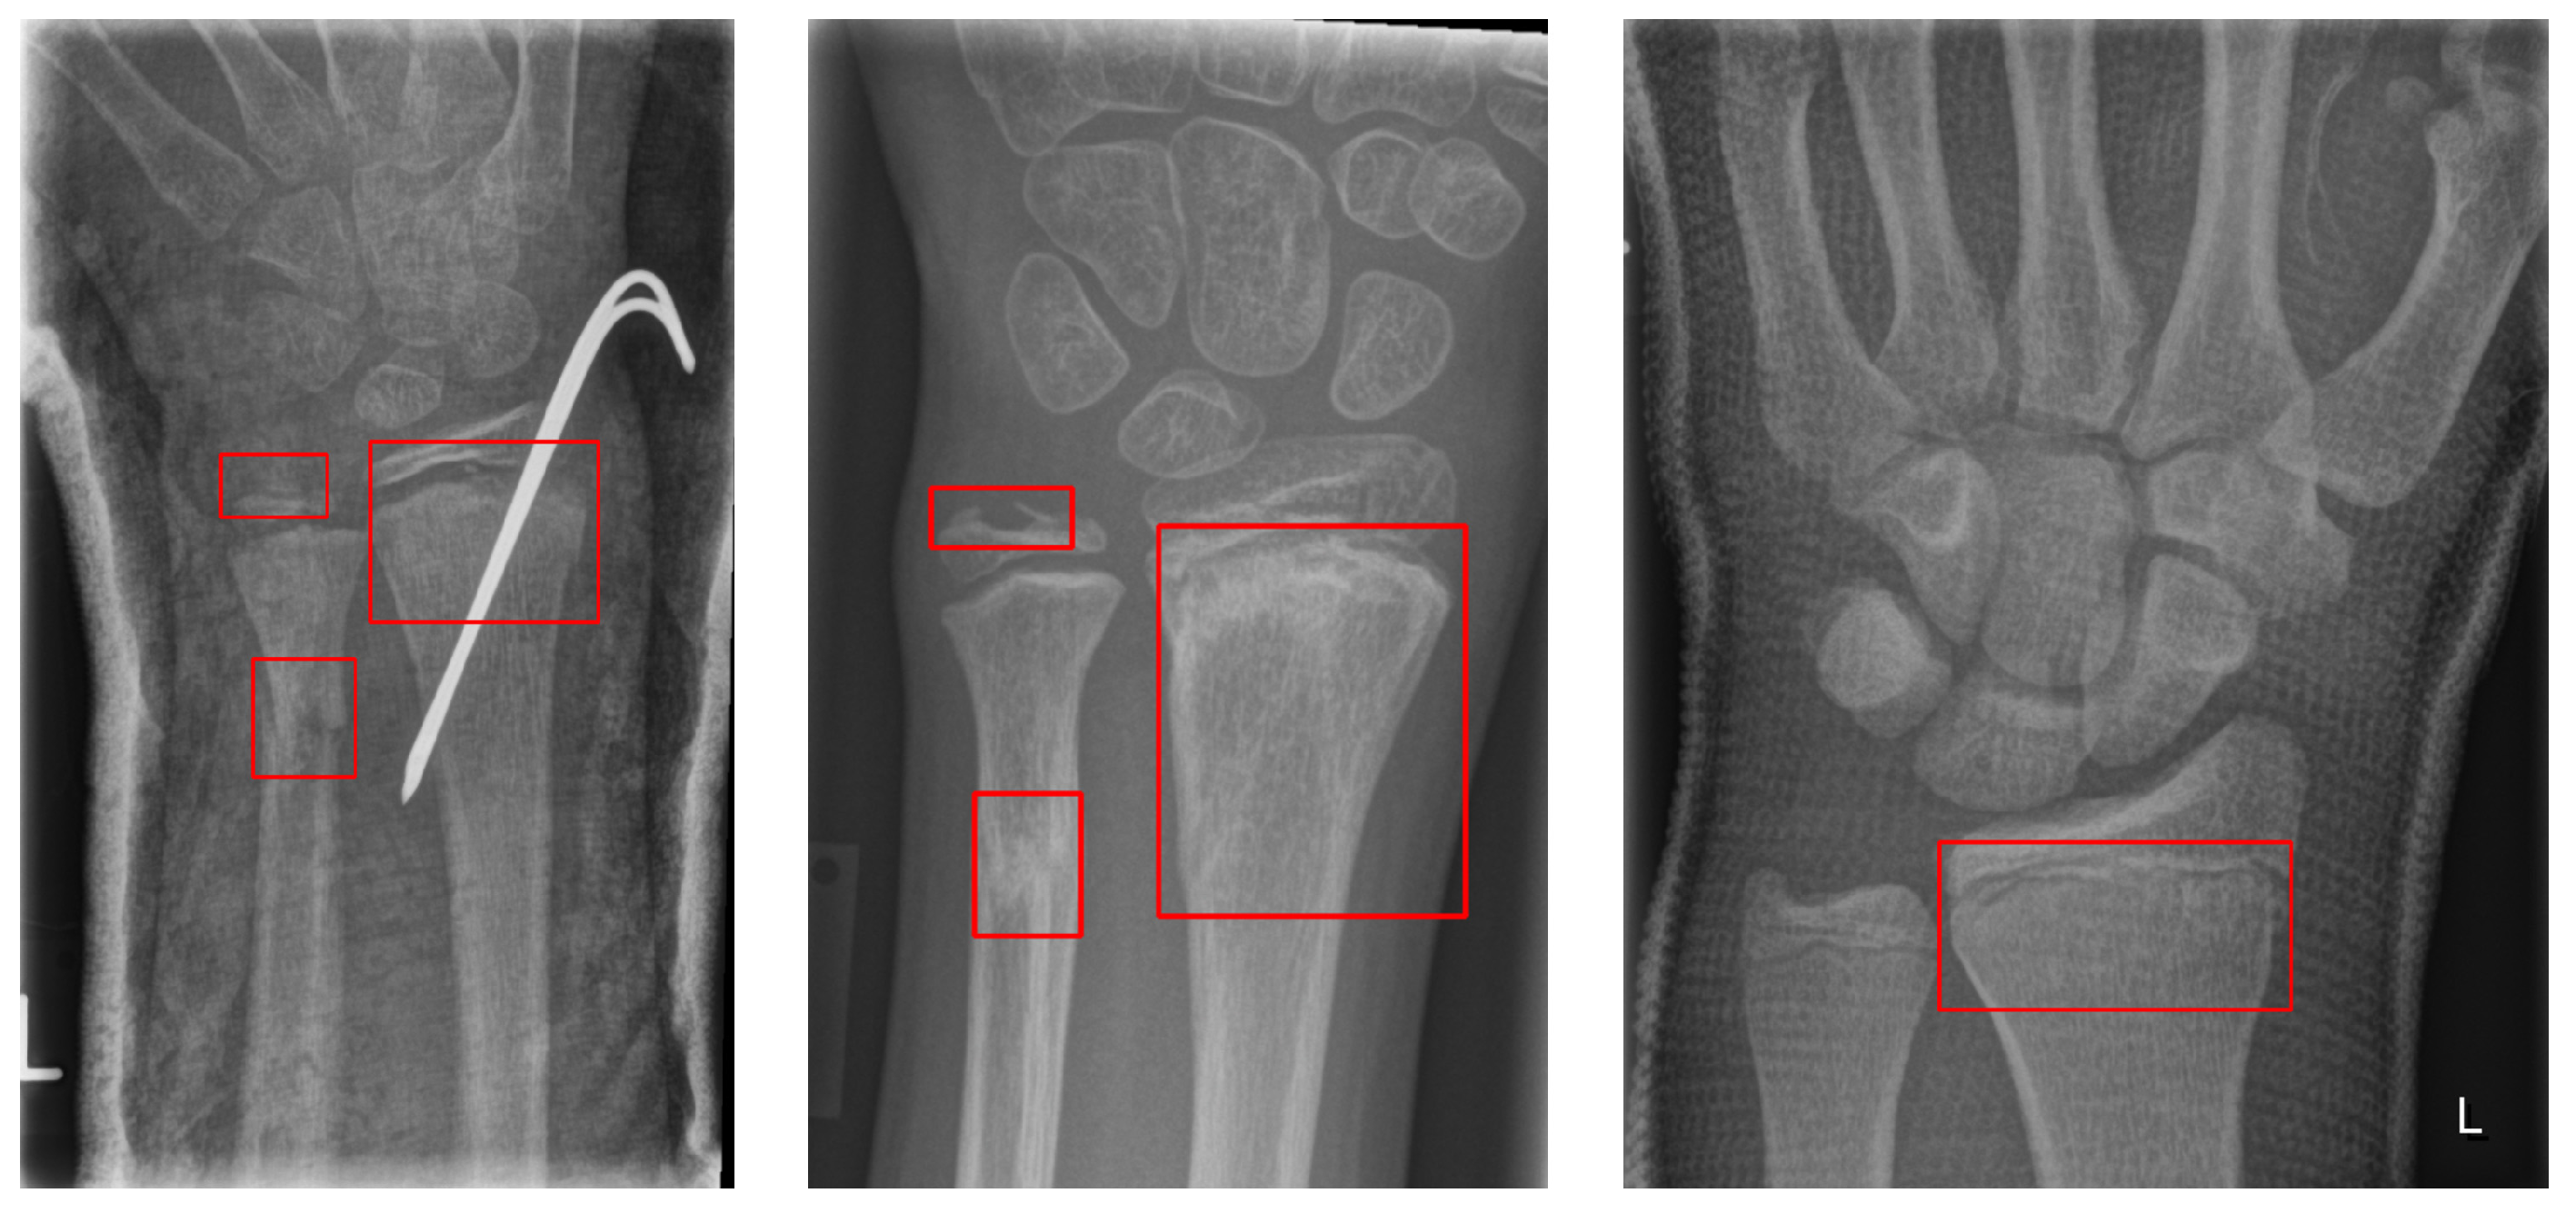

The GRAZPEDWRI-DX dataset consists of 6091 pediatric trauma wrist radiographs treated at the Department of Pediatric Surgery, University Hospital Graz, between 2008 and 2018. In total, 74,459 image tags were assigned to the 20,327 images. These tags included bone anomaly, bone lesion, foreign body, fracture, metal, periosteal reaction, pronator sign, soft tissue, text, and centerline. Of these, 18,090 boxes were marked as fractures, and 13,550 images had one or more fracture boxes. These were reviewed at least twice by a pediatric radiologist. The authors made the data publicly available. Figure 2 shows an example of multiple bounding boxes in one of the GRAZPEDWRI-DX datasets.

Figure 2. GRAZPEDWRI-DX dataset with the red box indicating the ground truth fracture region.